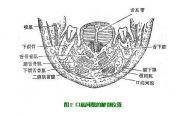

舌下間隙感染

628健康網(wǎng)為您分享有關(guān)舌下間隙感染的癥狀,舌下間隙感染的治療方法,舌下間隙感染的預(yù)防知識(shí),舌下間隙感染的癥狀圖片,舌...

下頜下間隙感染

628健康網(wǎng)為您分享有關(guān)下頜下間隙感染的癥狀,下頜下間隙感染的治療方法,下頜下間隙感染的預(yù)防知識(shí),下頜下間隙感染的癥狀...

口底多間隙感染

628健康網(wǎng)為您分享有關(guān)口底多間隙感染的癥狀,口底多間隙感染的治療方法,口底多間隙感染的預(yù)防知識(shí),口底多間隙感染的癥狀...